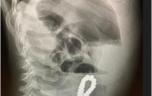

Les enfants sont les premiers concernés par les ingestions d’objets. Ils représentent 80 % des personnes qui ingèrent des corps étrangers, les plus nombreux appartenant à la classe d’âge compris entre 6 mois et 3 ans.

80 à 90 % des objets ingérés passent spontanément dans le tube digestif sans nécessiter de manœuvres médicales pour les retirer ; la chirurgie n’est requise que dans moins de 1 % des cas.

La liste en est longue, il s’agit souvent de pièces de monnaie, de boutons, de piles, d’aiguilles, d’arêtes de poisson, d’os, de crayons, de parties ou de pièces de jouets en plastique ou en bois… Mais aussi de dosettes de lessive, de médicaments, de barrettes de cannabis… qui font en plus courir un risque d’intoxication.

Quelles sont les complications ?

Les objets très volumineux, pointus ou coupants sont à l’origine des complications. L’enfant peut se plaindre d’une douleur dans la gorge lors de la déglutition ou dans l’œsophage ou encore derrière le sternum, avoir une difficulté à avaler, parfois des vomissements.

Si l’objet est bloqué dans le pharynx, la respiration peut devenir difficile avec survenue d’une toux persistante.

L’ingestion de piles est aussi source de complications. Les piles boutons provoquent des brûlures électriques ou par libération de substances (soude, sels de métaux lourds).